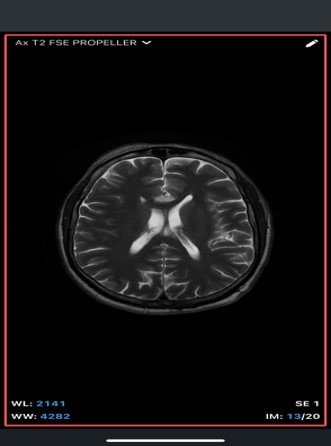

An extra-axial TI/T/Flair hyperintense lesion in midline at the inferior edge of the interhemispherie fissure extending along the superior margins of the corpus callosum with areas of blooming consistent with calcification and no post contrast enhancement –likely pericallosal lipoma.

• MRI

• T1-weighted: Hyperintense (fat signal).

• T2-weighted: Variable, usually hyperintense; may show chemical shift artifacts.

• Fat-suppressed sequences: Complete signal suppression confirms fat composition.

• Post-contrast: No enhancement.